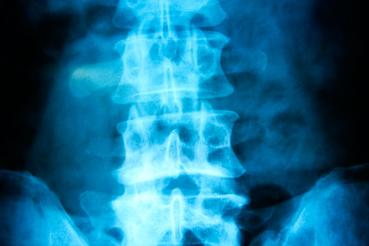

If you have persistent back pain, or if back pain is keeping you from working or being active, Dugan recommends getting help, and seeing a physiatrist is a great first step.

Physiatrists use nonsurgical approaches to address a full range of issues, from back pain to pelvic floor issues to migraines. They will assess your pain, figure out what's causing it, come up with a plan to relieve it (or refer you to a surgeon if the issue does require surgery) and educate you on how to keep it from coming back.